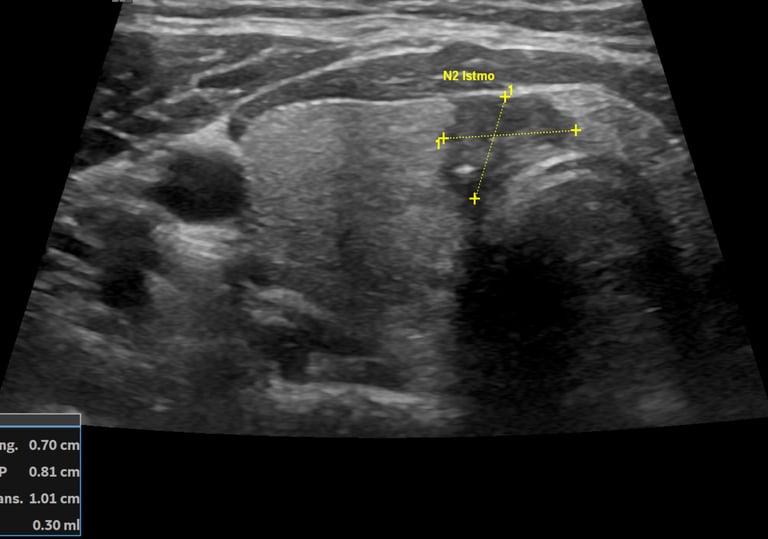

Existem critérios ultrassonográficos, isto é, características visualizadas ao exame de ultrassonografia dos nódulos da tireoide que sugerem ou não uma melhor investigação com a PAAF. Esses critérios levam em conta todas as caraterísticas dos nódulos da tireoide, dentre elas, destacamos:

Nódulo sólido, misto ou cisto;

Ecogenicidade, se o nódulo é mais escuro(hipoecoico), claro(hiperecoico) ou tons de cinza parecido(isoecoico) que a tireoide;

Formato. Se é maior na largura ou altura;

Margens. Se as margens do nódulo podem ser bem definidas, ou lobuladas, ou com extensão para outros tecidos;

Se possuem calcificações. Micro ou macro calcificações.

Obs.: Em negrito, são as características do nódulo na imagem acima.

Essas características ultrassonográficas levam a uma classificação chamada Ti-Rads, que vai de 1 a 5 muito utilizada pelos médicos radiologistas e que estão em todos os laudos de exames de ultrassonografia de tireoide.

Imagem: Nódulo Ti-Rads 5